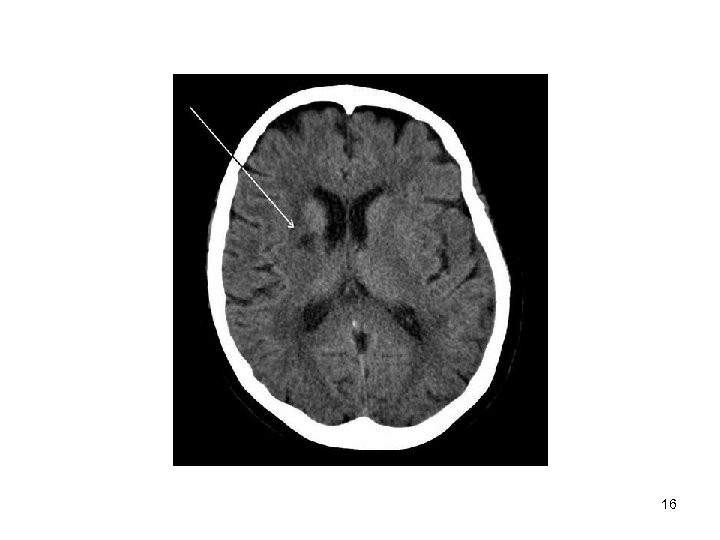

Lacunar Strokes